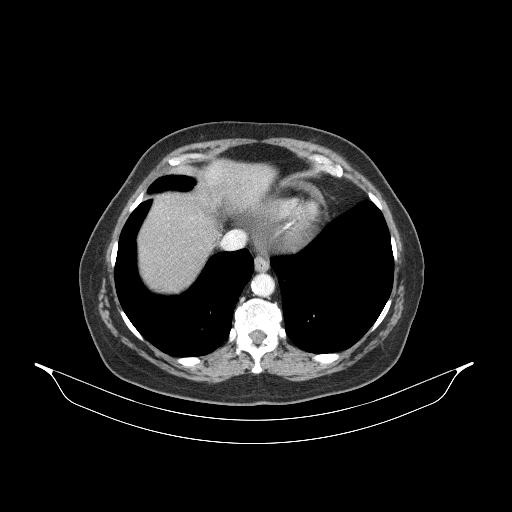

Reconstructed NATIVE CT scan (cycle consistency)

Full window (WL 1023.5, WW 4095 β†’ Low βˆ’1024, High +3071)

Actual HU range: [-863.7, 702.5]

Lung window (WL -600, WW 1500 β†’ Low βˆ’1350, High +150)

Actual HU range: [-863.7, 150.0]

Mediastinum window (WL 40, WW 400 β†’ Low βˆ’160, High +240)

Actual HU range: [-160.0, 240.0]